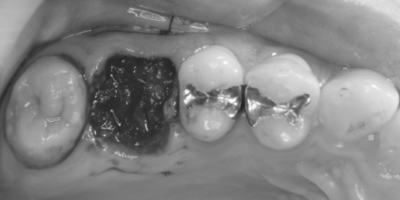

初診時デンタルX線写真

初診時デンタルX線写真とCT画像。

根管外に不透過像とそれを取り囲む透過像を認める。

コアを除去すると、分岐部へつながるパーフォレーションを認めた。

これが排膿の原因であったため、保存は困難と判断した。